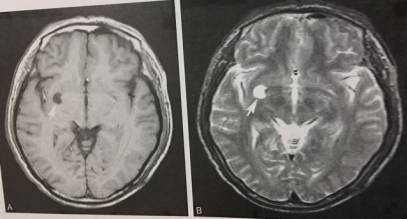

3、血管周围间隙扩大,VR

T1WI显示右侧基底节外下部类圆形低信号灶,T2WI呈高信号。